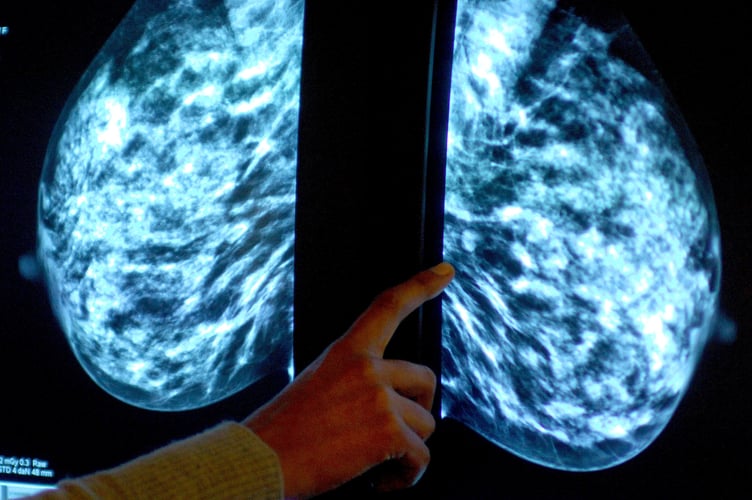

Breast screening uptake in Devon remains below pre-pandemic levels, new figures show.

Anyone registered with a GP as female will be invited for NHS breast screening every three years between the ages of 50 and 71.